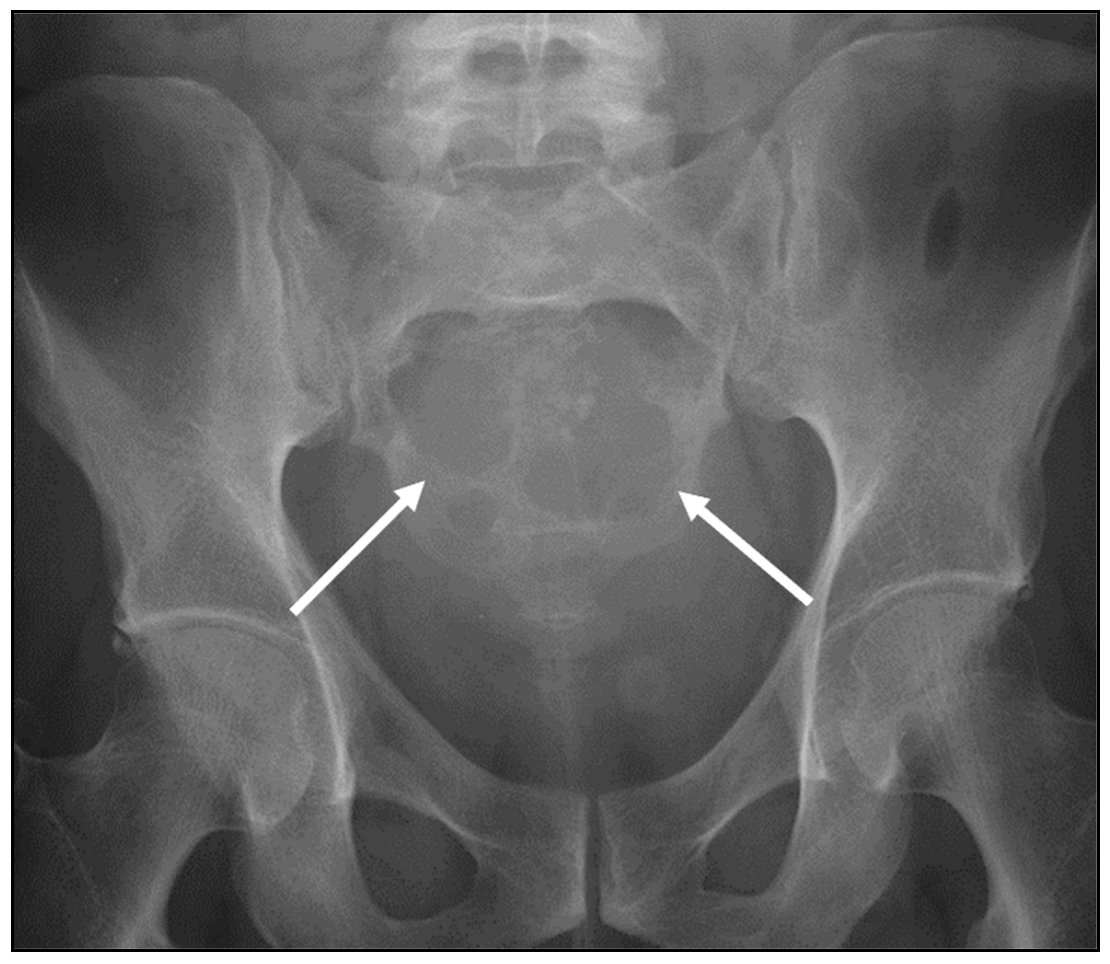

| Chondrosarcoma | Lytic lesion. ‘Rings and arcs’ calcification characteristic of chondroid matrix. | High T2 signal due to cartilage and myxoid content. Peripheral and septal enhancement. Enhancing extra-osseous soft tissue component. |